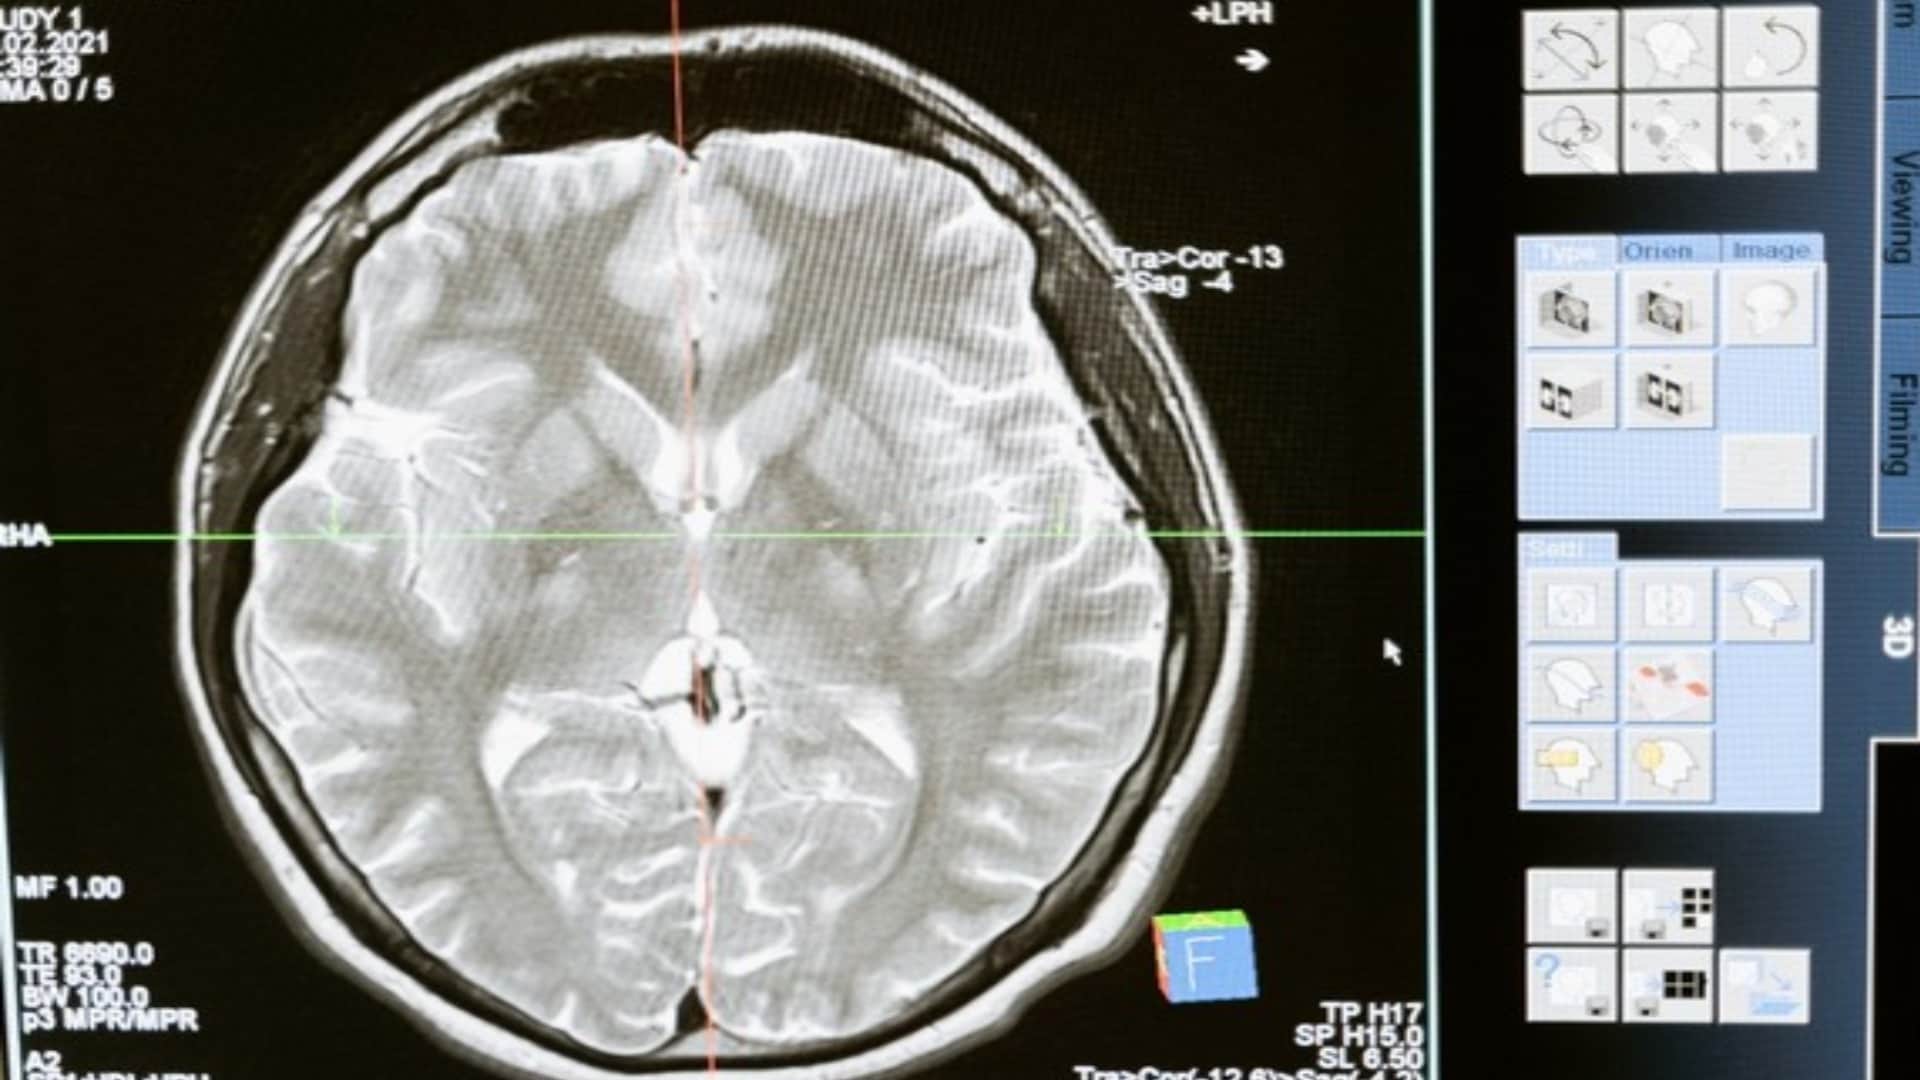

ब्रेन ट्यूमर जो मस्तिष्क में शुरू होते हैं उन्हें प्राइमरी ब्रेन ट्यूमर कहा जाता है। कभी-कभी, कैंसर शरीर के अन्य भागों से भी मस्तिष्क में फैलता है, ये ट्यूमर सेकेंडरी ब्रेन ट्यूमर होते हैं। मस्तिष्क में ट्यूमर का आकार बहुत छोटे से लेकर बड़ा तक होता है। इसकी समय पर पहचान हो जाए तो सर्जरी और अन्य इलाज के माध्यम से ट्यूमर को निकाला जा सकता है और रोगी की जान बचाई जा सकती है।

क्लीवलैंड क्लिनिक की रिपोर्ट के अनुसार केवल एक तिहाई ब्रेन ट्यूमर ही कैंसर का कारण बनते हैं, लेकिन चाहे वे कैंसरयुक्त हों या नहीं, ब्रेन ट्यूमर मस्तिष्क के कामकाज और आपके स्वास्थ्य को कई तरह से प्रभावित कर सकते हैं। ट्यूमर जब बडे़ हो जाते हैं तो इसके कारण आस-पास की नसों, रक्त वाहिकाओं और ऊतकों पर असर पड़ने लगता है, यही कारण है कि इसका समय पर निदान और इलाज जरूरी हो जाता है।